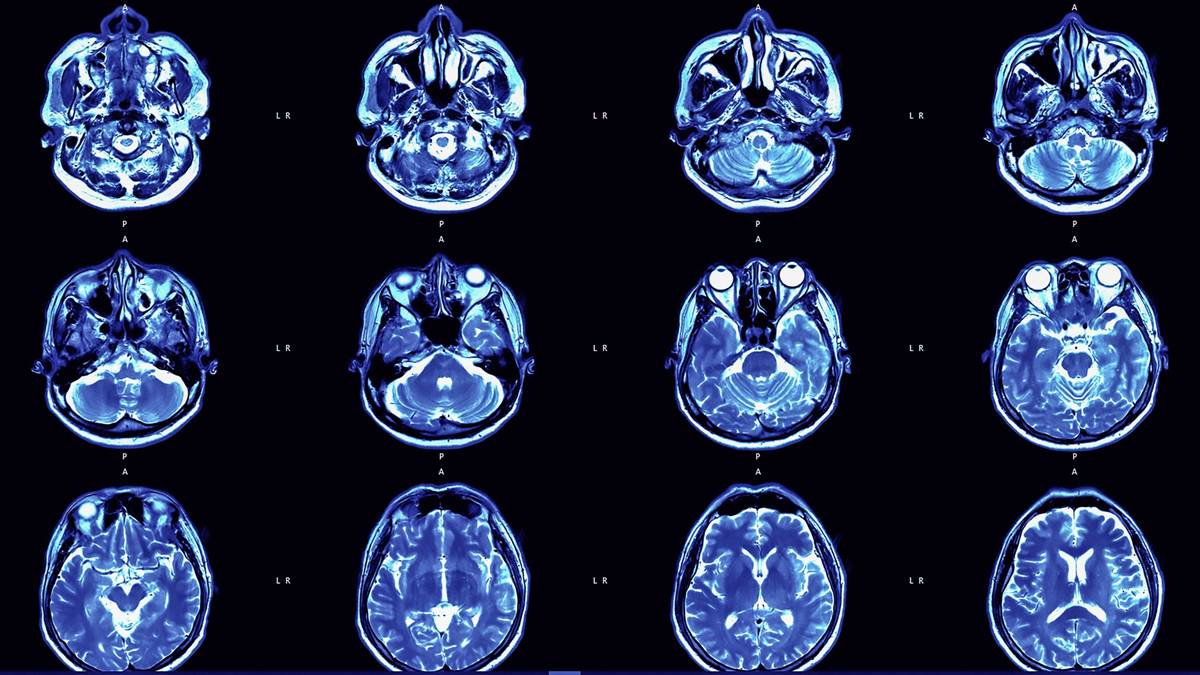

Agykutatás. Illusztráció. Fotó: Internet

A Nottinghami Egyetem kutatói Ali-Reza Mohammadi-Nejad vezetésével közel 15 ezer agyi képalkotó felvételt elemeztek mesterséges intelligencia segítségével. A céljuk az volt, hogy feltárják, milyen szerkezeti változások történnek az agyban az öregedéssel, és hogy a világjárvány milyen hatással lehetett erre a folyamatra.

A kutatás során a szakértők a brit UK Biobank program 996 résztvevőjének agyi felvételeit vizsgálták.

A résztvevők egyik csoportja a járvány kitörése előtt (2020 márciusa előtt) készült két agyi vizsgálat eredményét adta, míg a másik csoportnál az első vizsgálat 2020 előtt, a második pedig azt követően történt, átlagosan három év különbséggel – számol be róla a New Scientist.

Az eredmények meglepőek: azoknál, akik a járvány időszakában élték meg a második vizsgálatot, az agyuk szerkezete átlagosan 5,5 hónappal idősebbnek tűnt, mint azoké, akiknél mindkét vizsgálat még a pandémia előtt történt.

Ez a változás főként az agy fehér- és szürkeállományát érintette.